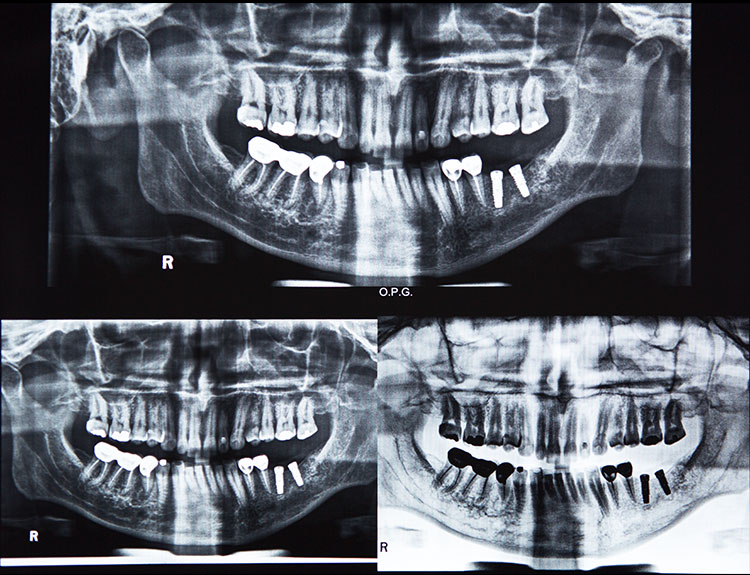

Dental implants are artificial tooth roots made of medical-grade titanium that are surgically placed into the jawbone. Once the implant integrates with the bone, a crown is fixed on top, giving you a strong, natural-looking replacement tooth.